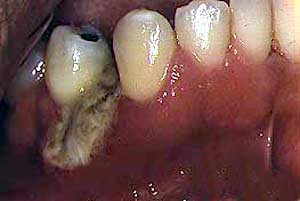

Secuestro óseo |

Ocasionalmente otras bacterias pueden presentar ulceración oral

como el mycobacterium avium intracellularae, mycobacterium

tuberculosis, E.coli, actinomyces, Klebsiella y pseudomonas.

Se ha descrito en un número pequeño de casos, Angiomatosis bacilar

oral causado por Rochalimaea henselae. |